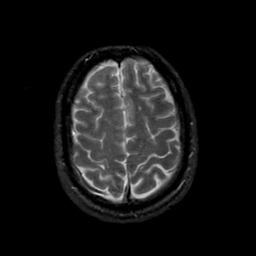

MR Study #21, November 3, 1991 -- Slice #40